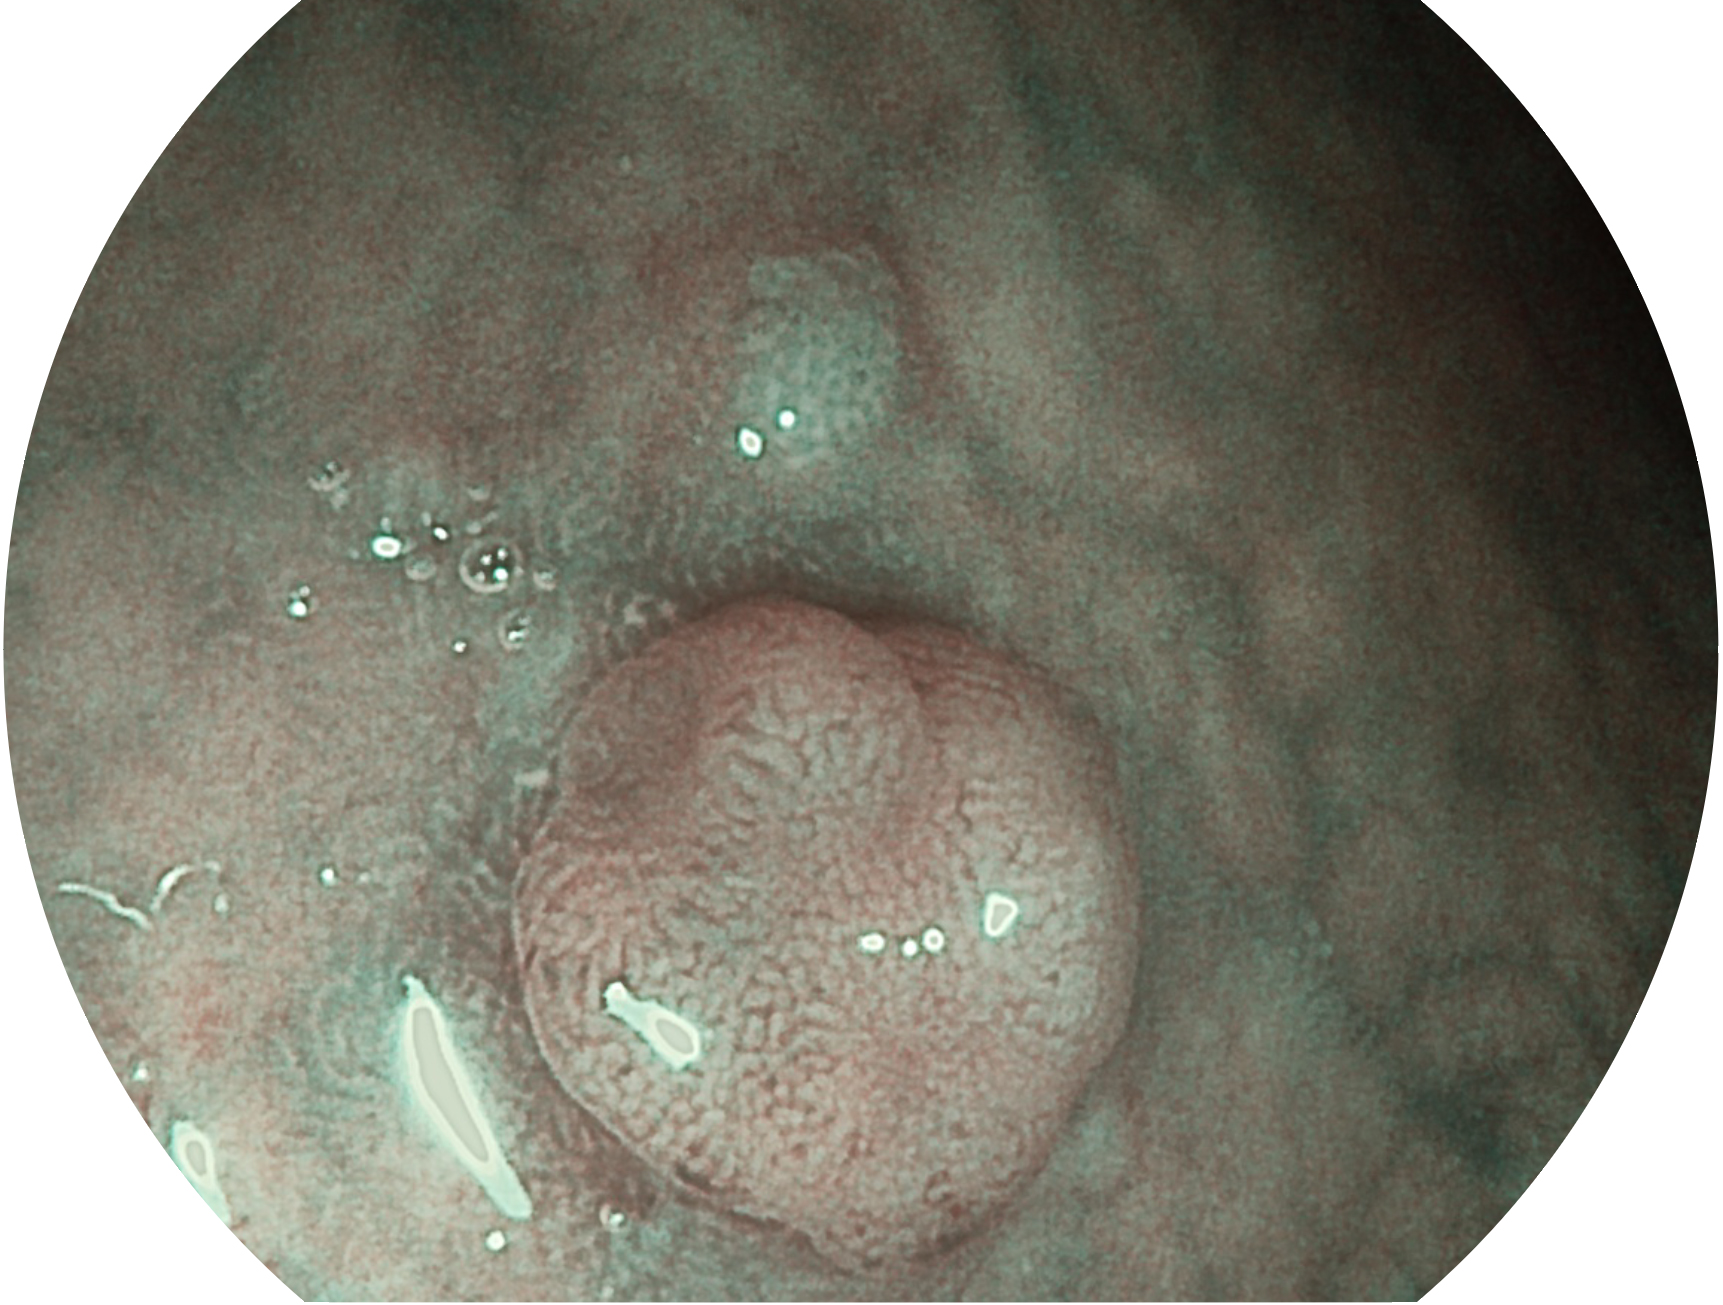

狗万官方网站新开发的内镜染色技术,主要是基于多波长LED 光源的开发,VLS-55Q 四波长LED 光源是由四个不同颜色的LED光按照相应照明模式所规定的特定发光比例进行合束后形成,合束后形成的照明光的光谱由红光、绿光、蓝光及蓝紫光这四个不同的波段范围构成。具有更高光谱自由度,通过光谱比例的控制,实现了聚谱成像技术,英文全称为“Spectral Focused Imaging, SFI”,缩写为“SFI”和光电复合染色成像技术,英文全称为“Versatile Intelligent Staining Technology, VIST”,缩写为“VIST”。